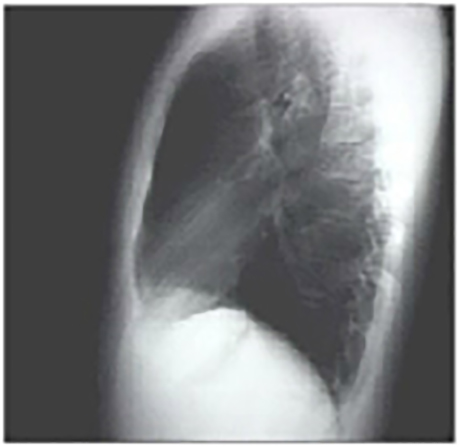

The lateral view is normal, with no evidence of chamber enlargement including the normal anterior shadow of the right ventricle and posteroinferior shadow of the left ventricle.